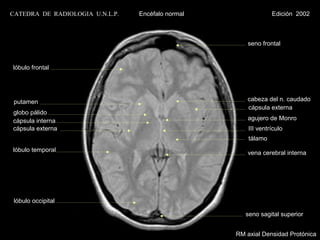

seno frontal

lóbulo frontal

putamen                                              cabeza del n. caudado

cápsula externa

globo pálido

cápsula interna                                       agujero de Monro

cápsula externa                                        III ventrículo

tálamo

lóbulo temporal                                       vena cerebral interna

lóbulo occipital

seno sagital superior

RM axial Densidad Protónica